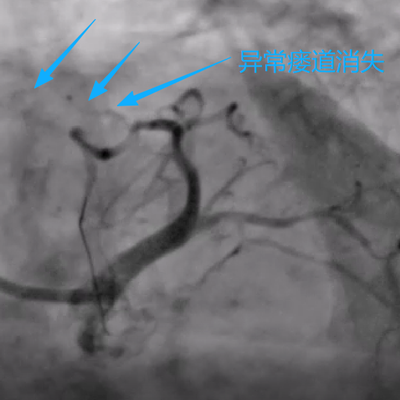

手术当日,在数字减影血管造影(DSA)设备的精确引导下,手术团队通过患者手腕部仅有米粒大小的穿刺点,将一根细如发丝的微导管,犹如“穿针引线”般精准送达深藏在心脏的异常瘘管内。随后,通过导管将栓塞物质置于瘘管的关键部位,成功实现了对异常通道的“精准封堵”。术后即刻造影显示,异常血流分流完全消失,被“盗走”的血液重新回到了正常的冠脉轨道,手术取得圆满成功。(如下图)

“整个手术过程患者处于清醒状态,创伤小、痛苦少、恢复快。” 心血管内科朱兴彪主任表示,“术后第二天,患者即可下床活动,之前胸闷气促的症状得到了立竿见影的缓解,患者和家属都非常满意。”